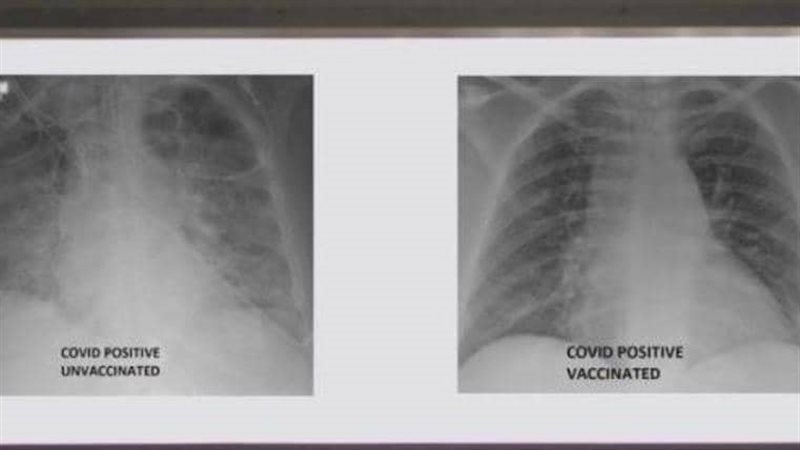

صور أشعة توضح الفرق بين رئتي شخص مطعم ضد كورونا وآخر غير محصن

نشر الطبيب العربي في الولايات المتحدة، غسان كمال، صورة تظهر الفرق بين رئتي شخص جرى تطعيمه ضد فيروس كورونا ورئتي شخص آخر لم يتلق التطعيم، مشيرا إلى أن الاثنين أصيبا بفيروس كورونا.

أثر كورونا على الرئتين

وأظهرت صور الأشعة السينية، أن رئتي الشخص غير الملقح، المصاب بفيروس كورونا كانت بيضاء بصورة شبه كاملة وتعرف بـ"عتامة الرئة"، مما يعني أنها كانت غارقة في الفيروس، في حين أبرز صور رئتي الشخص ببيضاء أقل.

وتعني صورة الأول أيضا نقصا في دخول الهواء إلى رئتيه، فيما تعني لدى الثاني أن الهواء يتدفق بسهولة علاوة على أن رئتيه خاليتين من الوباء.

ويعمل غسان كمال، وهو من أصول لبنانية، مدير لوحدة العناية المركزة في مستشفى بولاية ميزوري، وهناك عالج آلاف المصابين بفيروس كورونا، منذ تفشي الوباء في أميركا ربيع عام 2020.

مضاعفات شديدة تضرب الرئتين

وغالبا ما تؤدي الإصابة بفيروس كورونا إلى مضاعفات شديدة تضرب الرئتين تحديدا مثل الإلتهاب الرئوي، الذي يحدث عندما تغرق الرئتان بالسوائل وتصبح ملتهبة.

العجز عن امتصاص الأكسجين

وعندما تمتلئ الأكياس الهوائية بالسوائل، تعجز عن امتصاص المزيد من الأكسجين، مما يؤدي إلى ظهور أعراض مثل السعال وضيق التنفس.

وأظهرت الدراسات أن كورونا يحدث تلفا في الخلايا الظهارية، التي توجد في الجهاز التنفسي ومهمتها منع دخول الفيروسات إلى الجهاز، وأشارت الدراسات إلى أن التلف يمتد من الأنف إلى الرئتين.

موجة جديدة من وباء كورونا

وتعرضت ولاية ميزوري الأميركية، مؤخرا، إلى موجة جديدة من وباء كورونا، حيث ارتفع متوسط الإصابات بنسبة 36 في المئة، من حدود 2100 يوميا إلى 2900.

وقال كمال في تصريحات لوسائل إعلام محلية، إن مرضى كورونا الذين يعالجهم كانوا أصغر سنا مما كانوا عليه في الشتاء الماضي وغالبيتهم لم يتلقوا اللقاح، مضيفا: "نرى مرضى جديدين".

آثار لقاح كورونا في رئتي الشخص

وأشار إلى أنه نشر الصور من أجل إظهار الفرق الذي يمكن أن يحدثه اللقاح في رئتي الشخص في حال إصابته بالفيروس، وهذا حتى يتعرف الجميع على الآثار التي تظهر على الرئة نتيجة اللقاح.